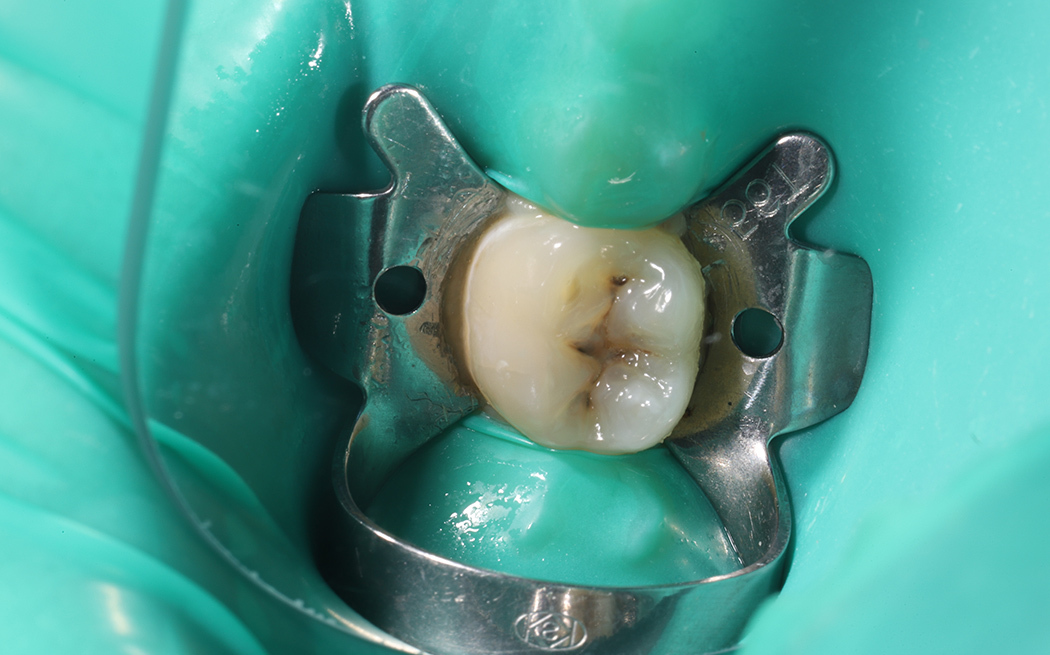

Препарирование и реставрация 36 зуба при вторичном кариесе с надежной изоляцией и полировкой пломбы